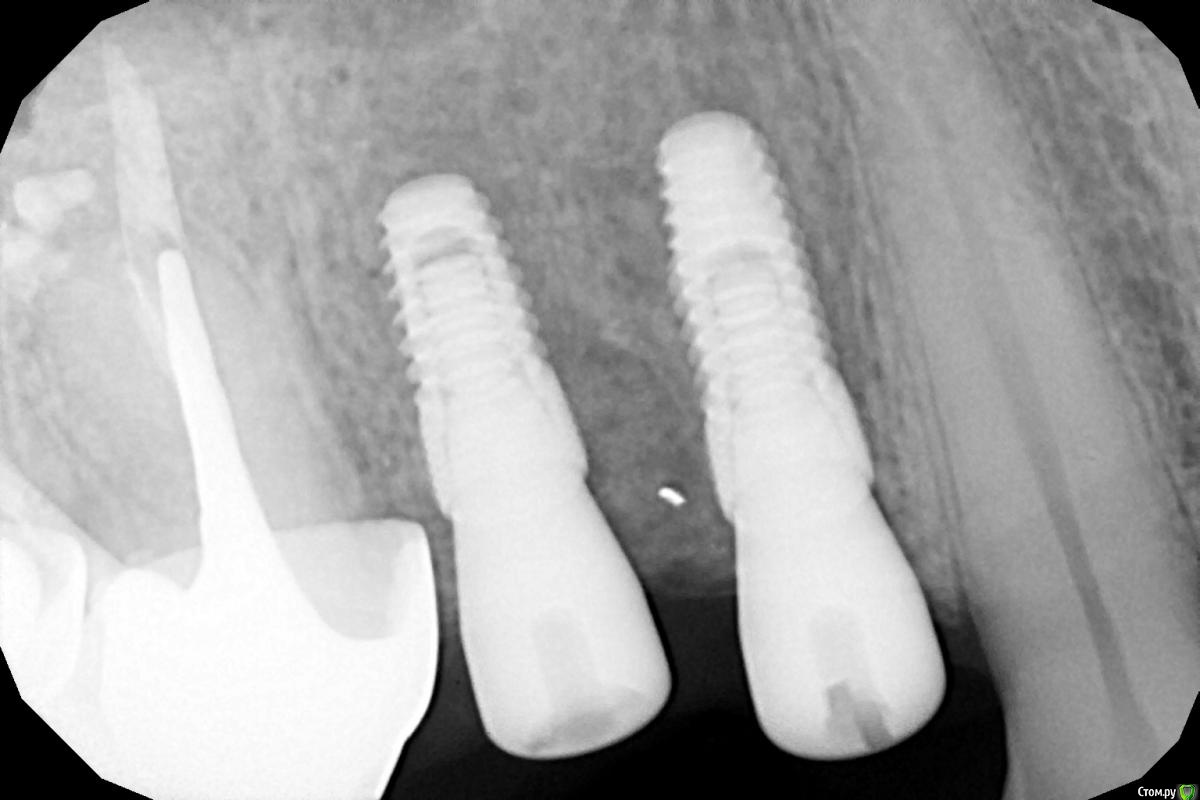

Женька Опубликовано 6 марта, 2021 Автор Поделиться Опубликовано 6 марта, 2021 (изменено) Почти получилось также как и планировалось по кт.Но выглядит прям вооообще нёбно кмк. Редукцию кости проводил, хотя это сложно наверное назвать редукцией.По снимкам кажется что сильно утопил, но по факту это из-за вестибулярного края так и кажется что отпиливать нужно было больше мне Изменено 6 марта, 2021 пользователем Женька Ссылка на комментарий